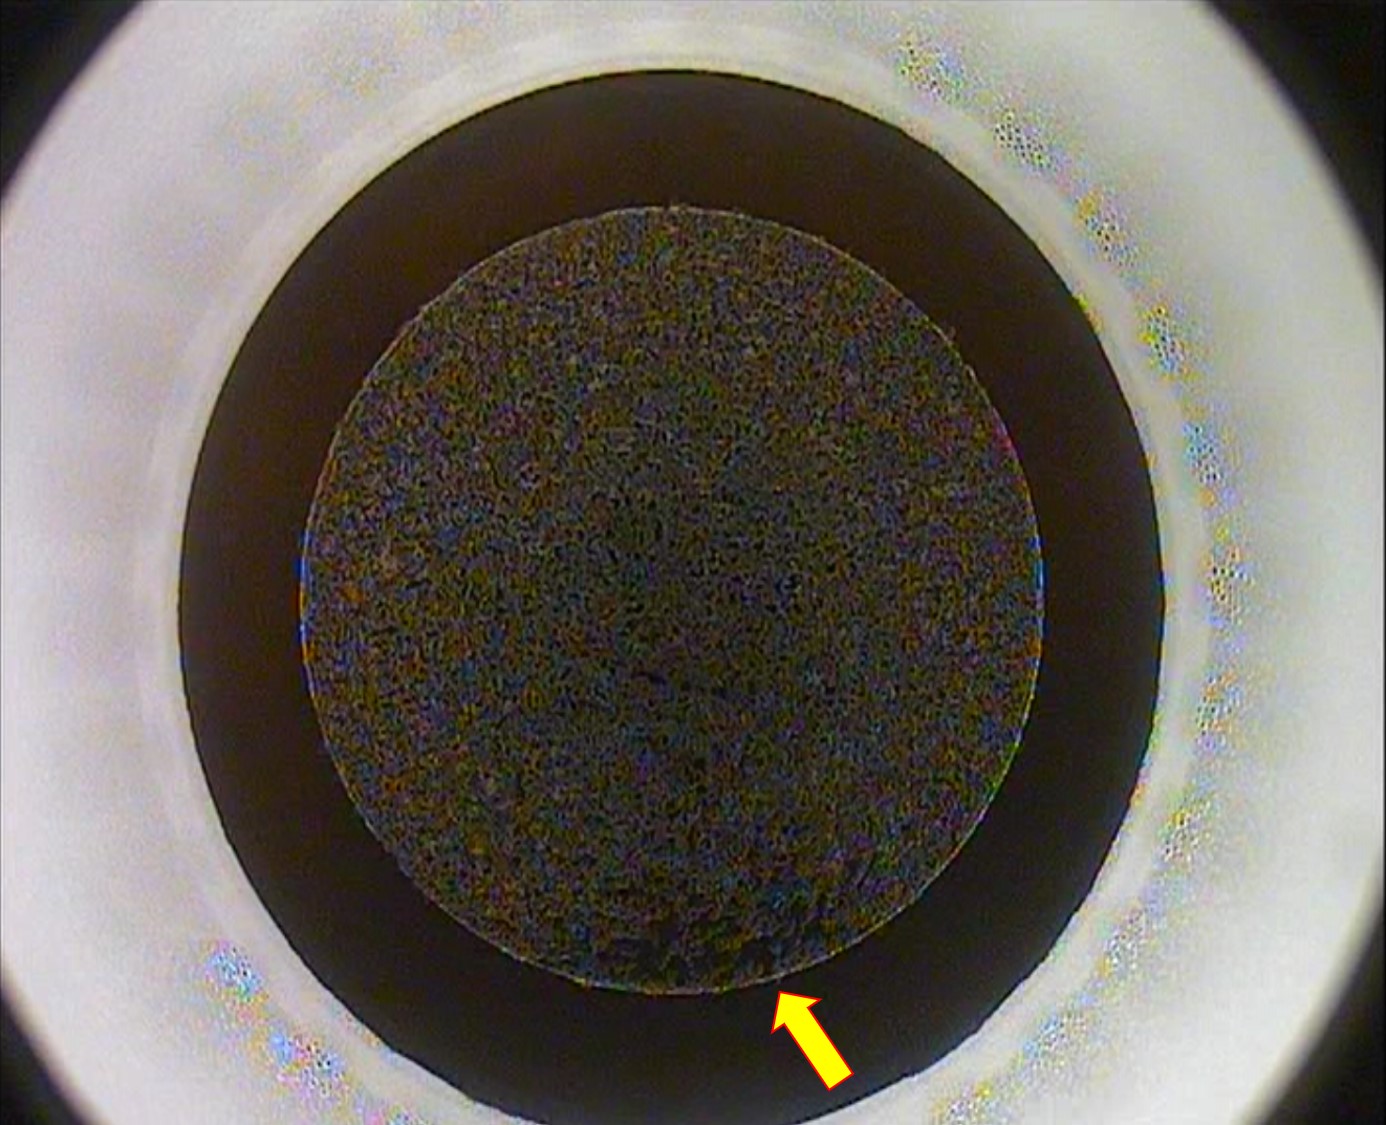

For femtosecond laser irradiation to be successful, a non-dry ocular surface and adequate femtosecond energy are important. If there is a foreign substance on the ocular surface or if it is too dry, there are areas (black spots in the pics) where the laser cannot be irradiated. In this case, it can be difficult for even an experienced surgeon to extract the lenticule. Therefore, it is important to proceed with the procedure (patient preparation, draping (+ speculum), docking & centration and Suction) before the laser process as quickly as possible, so that the laser process ends before the eyes dry out.